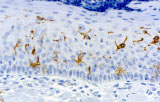

- Linfoma di Hodgkin classico: le cellule tumorali sono tipicamente CD30+ e spesso CD15+, con PAX5 debole e CD20 negativo nelle grandi cellule tumorali.